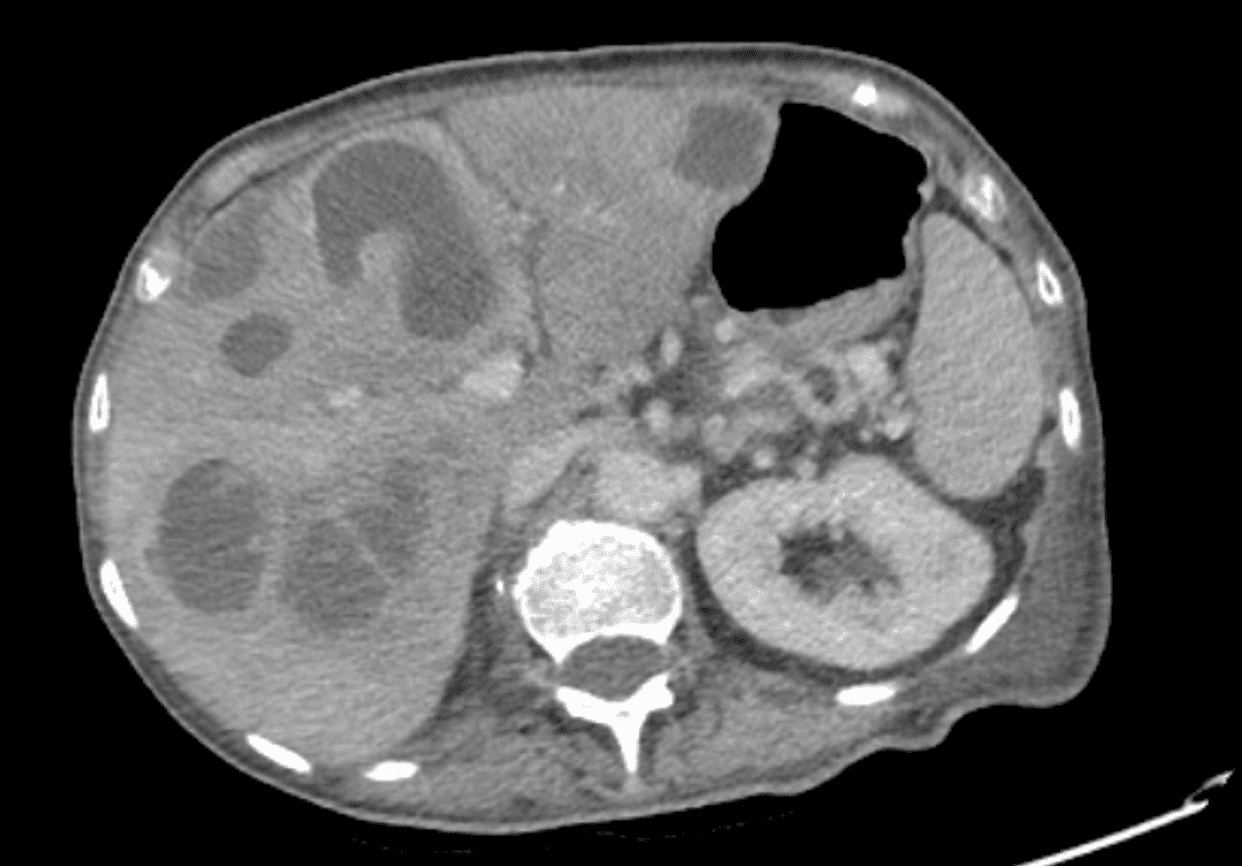

Se realiza una ecografía abdominal a pie de cama con hallazgo de múltiples imágenes hipodensas con contenido heterogéneo y áreas quísticas en hígado, sugestivas de metástasis, por lo que se solicita TAC abdominopélvico que confirma dichas lesiones con componente necrótico sobreinfectado y una con extensa neoplasia rectal localmente avanzada.

Probable neoplasia de recto localmente avanzada metastásica.

Como conclusiones me gustaría reforzar el uso de la ecografía clínica en urgencias ya que puede ser clave tanto para realizar diagnósticos que se pasarían por alto sin esta herramienta, como para acelerar procesos diagnósticos como en este caso.